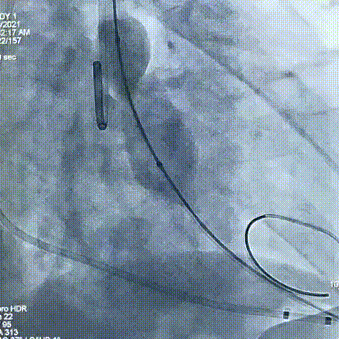

术中操作

球囊预扩

瓣膜定位

经评估后植入左主干烟囱支架